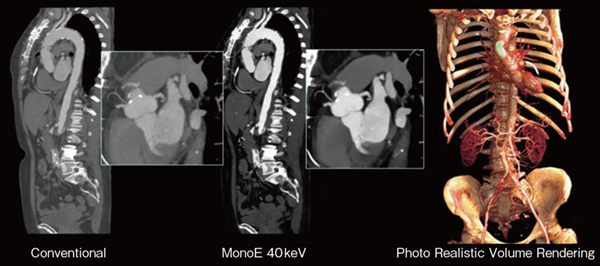

図3 Spectral CT 7500による大血管イメージング

100kVpを使用したスペクトラルスキャンにより心電図同期を行わず,同範囲で2秒未満の高速スキャンを実施し,ヨード造影剤量も60%低減されている。